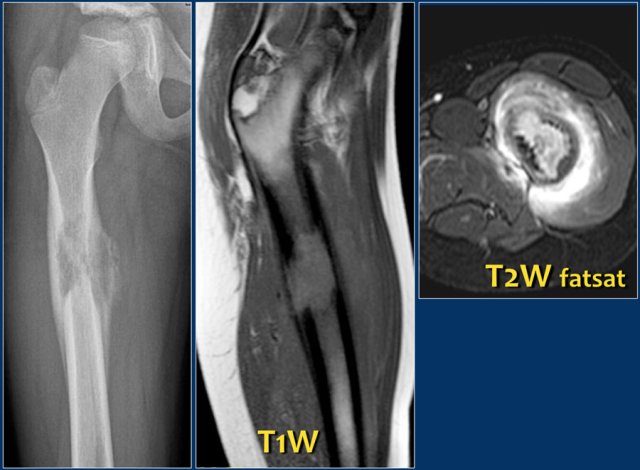

On x-ray there is a sharp defined oval lytic lesion with or without a sclerotic rim, with its long axis parallel to the long axis of the bone (see figure).

On MRI the lesion is hyperintense on T2WI. There is joint effusion and only minimal edema in the surrounding musculature.